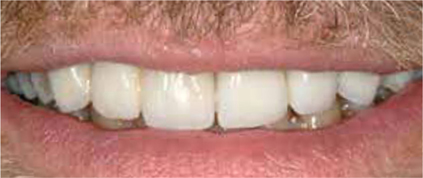

Afb. 1

De heer H. bij de intake.

Afbeelding vergroten